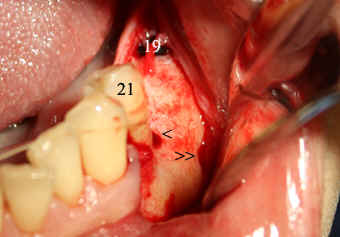

Fig.16 and 17 First of all, make an incision and raise the flap to expose the mental nerve (double arrowheads in Fig.16). Use this and neighboring landmarks (the tooth #21 and healing plug of implant #19) to make an initial osteotomy (single arrowhead). Insert a paralleling pin and take PA (Fig.17). Notice the angulation as compared to that in Fig. 8 and 9. The osteotomy needs to move distally using side-cutting bur: Lindemann (Brasseler). |